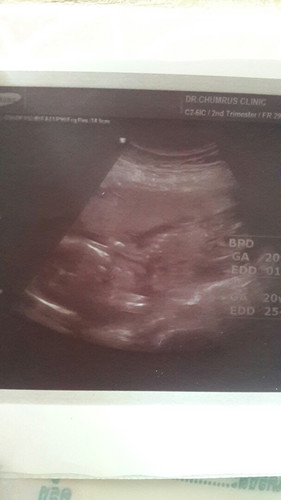

ไปซาวด์ดูเพศน้องมา แม่ๆพอจะดูออกกันไหมค่ะ??

ปล.คุณหมอบอกboyครับ?